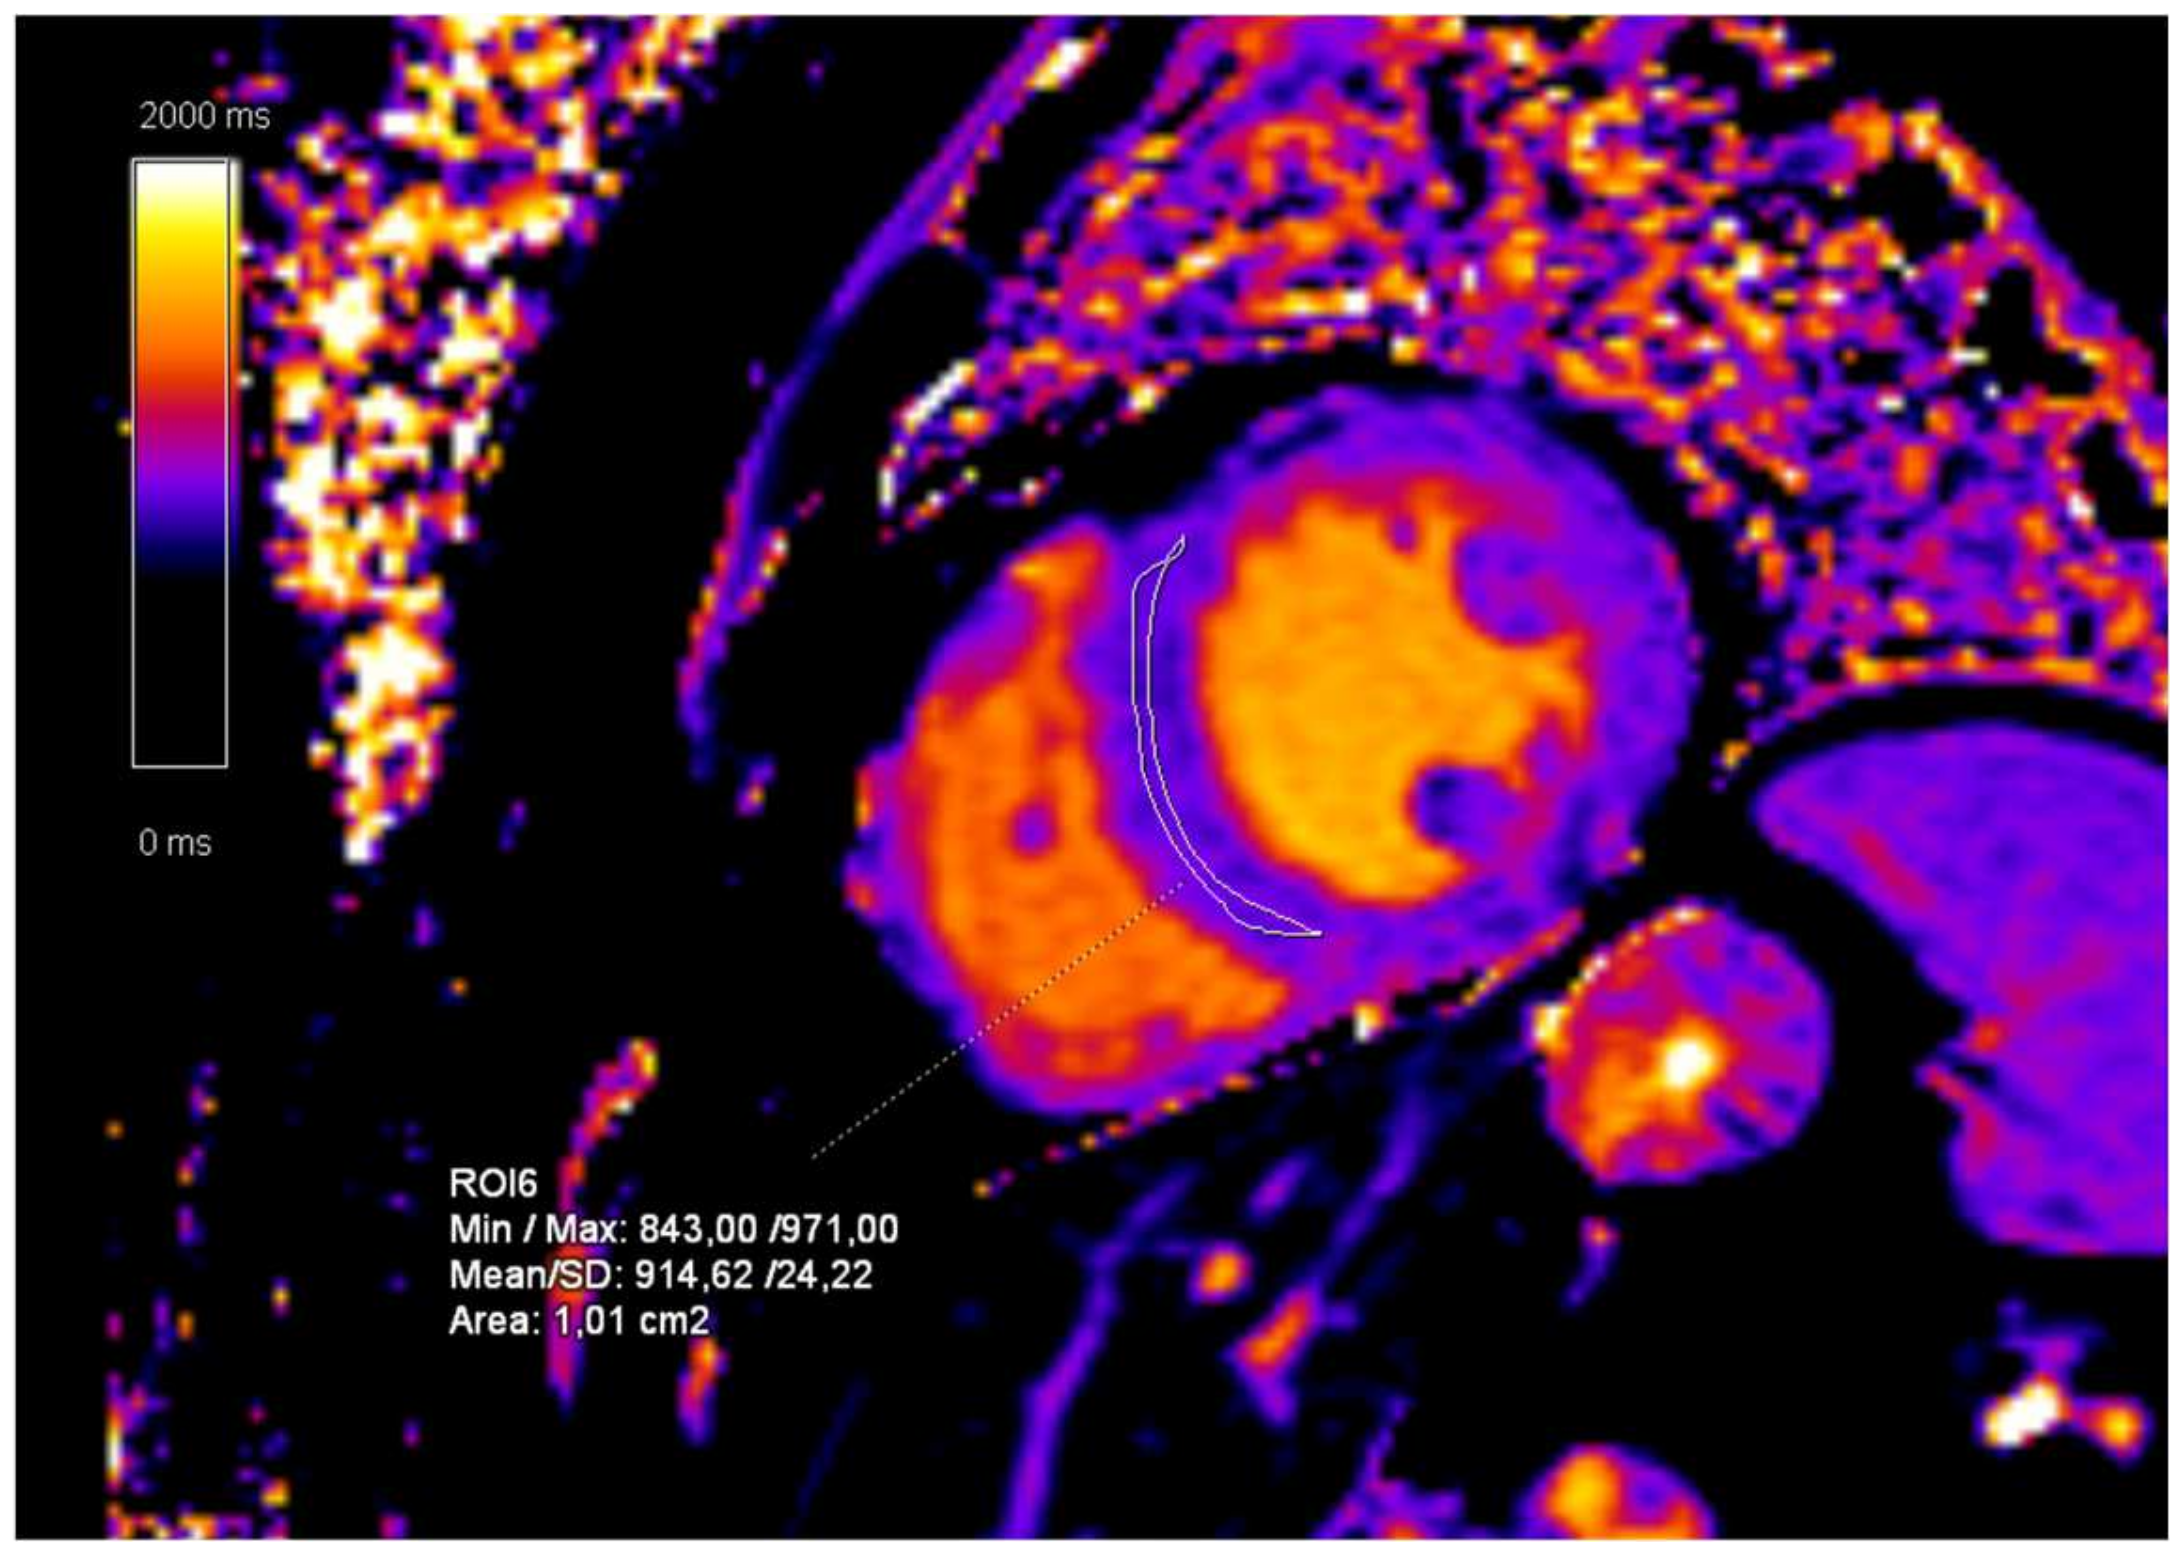

2. Case Presentation